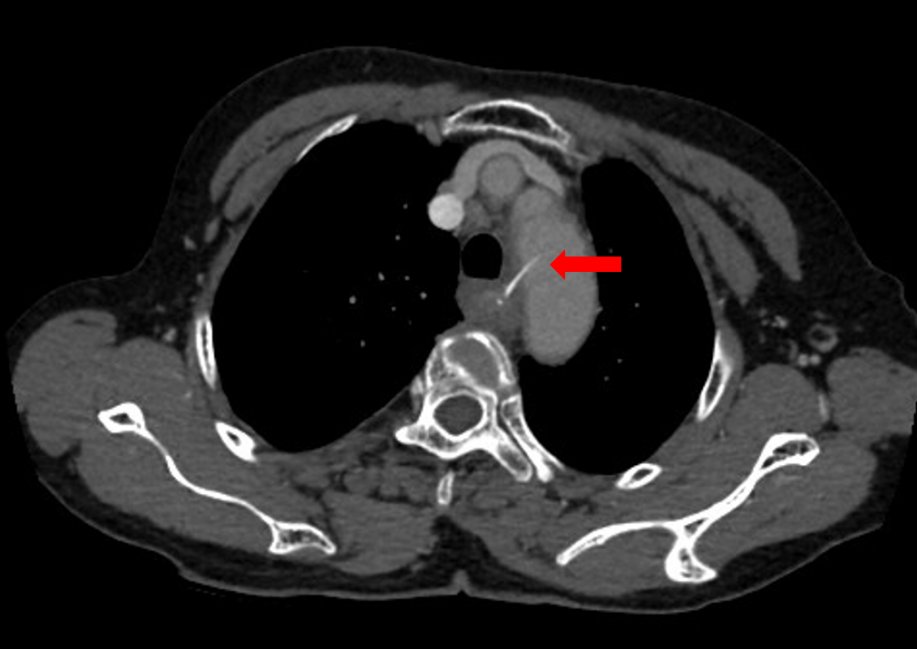

【 食管|女子硬吞饭团把鱼刺扎进主动脉医生:鱼刺卡喉后“土法”不可取】鱼刺卡在这个位置,很棘手,阿婆家附近的医院医疗技术有限,于是,匆匆来到广州医科大学附属第二医院(简称“广医二院”)耳鼻咽喉科就医。为了进一步明确鱼刺的位置,搞清楚它与大血管之间的关系,该科医师立即联系放射科为阿婆做胸部CT平扫+增强检查。值班医师阅片发现,鱼刺已穿破阿婆的食管壁和胸主动脉内侧壁!

CT显示鱼刺穿破阿婆的食管壁和胸主动脉内侧壁。